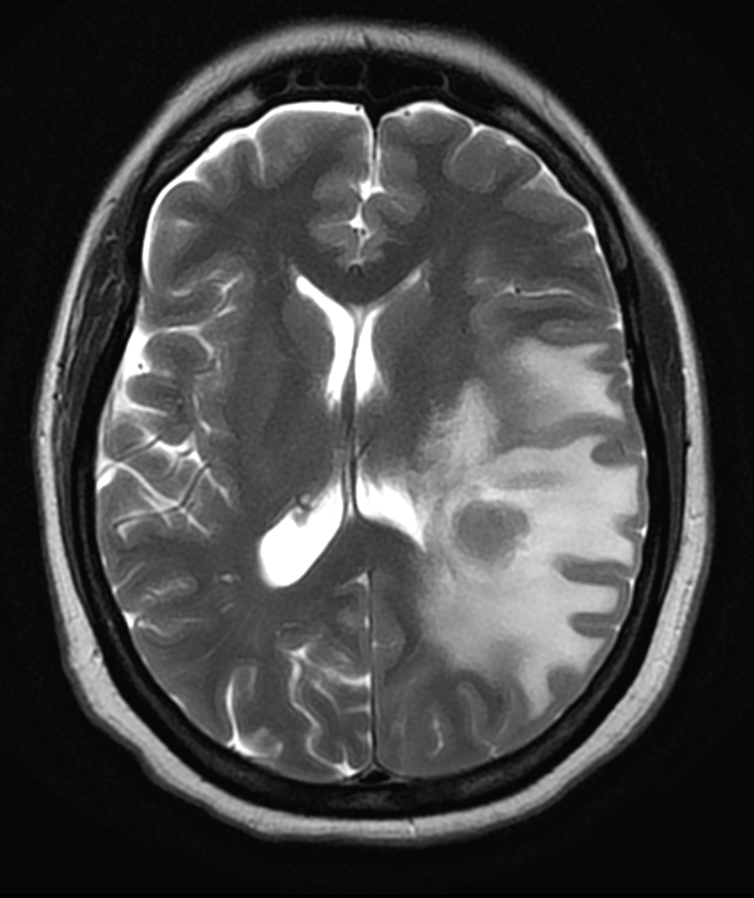

RM T2